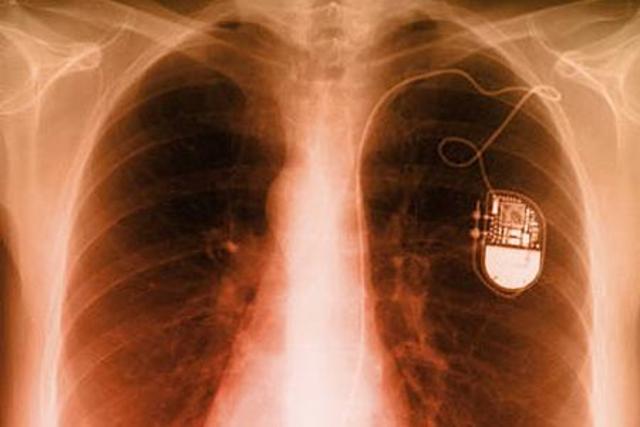

• Nachhilfe fürs Herz

Nachhilfe fürs Herz

‚Stolpert“ der Lebensmotor oder droht er, stehen zu bleiben, hilft vielen Betroffenen ein Herzschrittmacher. Schon 1932 hatte ein New Yorker Arzt ein Gerät beschrieben, das Herzen mit Hilfe von periodischen Strompulsen reizt. Erst 1958 gelang es jedoch Ingenieuren, Herzschrittmacher ausreichend klein zu entwickeln. Der schwedische Chirurg Åke Senning in Stockholm setzte einem Patienten erstmals einen Herzschrittmacher ein. Die ersten Geräte mussten allerdings nach 24 Stunden extern neu aufgelade